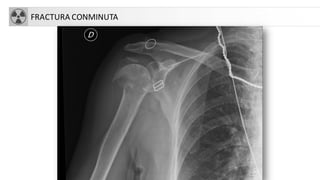

FRACTURA CONMINUTA

Fx CLAVICULA

• Fx habitualmente en 1/3 medio (85%), por traumatismo indirecto

FRACTURA HUMERO

• 5% de las fracturas del adulto, 75% en 1/3 superior

• Más frecuentes en ancianos (osteoporosis)

• Tratamiento:

• Conservador: cuello quirúrgico con impactación (ancianos)

• Quirúrgico: el resto

• Complicaciones

• Seudoartrosis

• Consolidación defectuosa

• Necrosis avascular

• Lesión nerviosa ó vascular

• Rigidez-capsulitis.

• Fx diáfisis: más frecuente en jóvenes o ancianos con fx patológica

FRACTURA ESCAPULA

• Traumatismo directo de alta energía. Se asocia a otras

fracturas-luxaciones de C. escapular ó tórax

(neumotórax…)

• Si no se piensa en esta posible fractura es muy difícil

detectarla

• Si afecta a cuerpo o espina (50%), tratamiento

conservador

• Si se afecta cuello o glenoides: valorar cirugía

• Consolidan a las 6 semanas